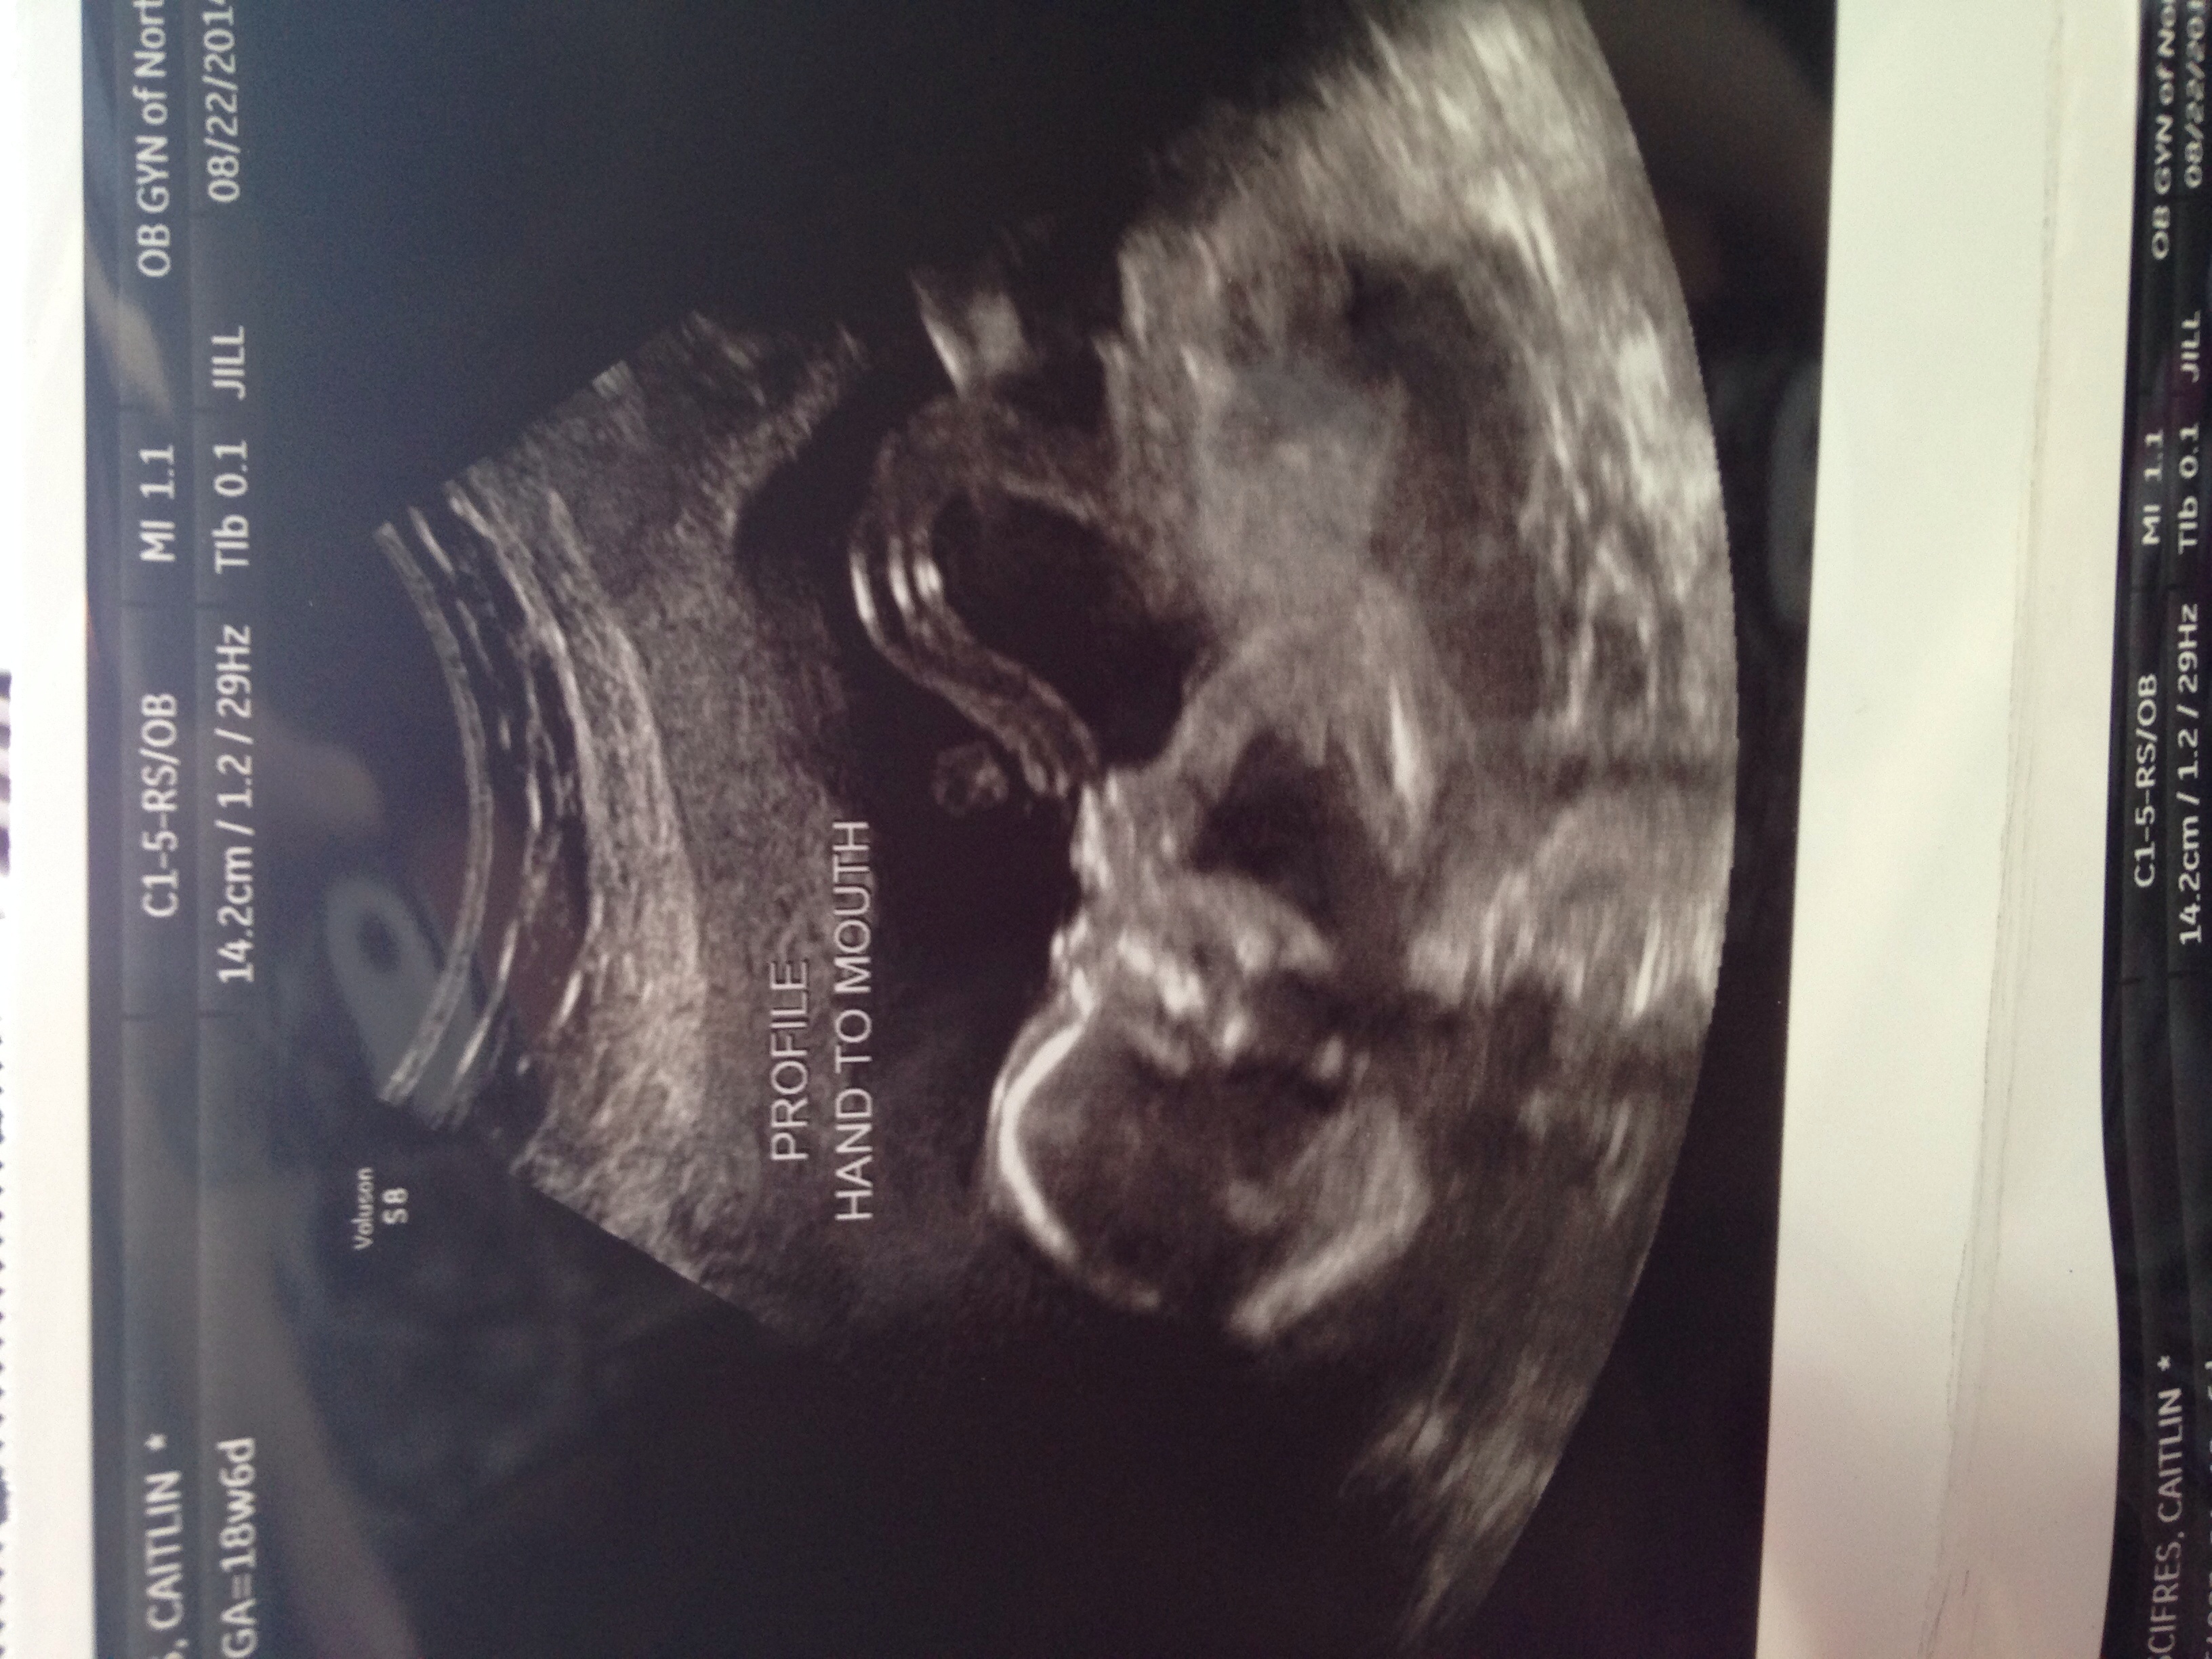

My u/s day went amazing. Being a FTM it was pretty much everything I expected. Baby was quite active and the tech said we had a tall baby on our hands! I posted a pic last week I do believe! Still team green!